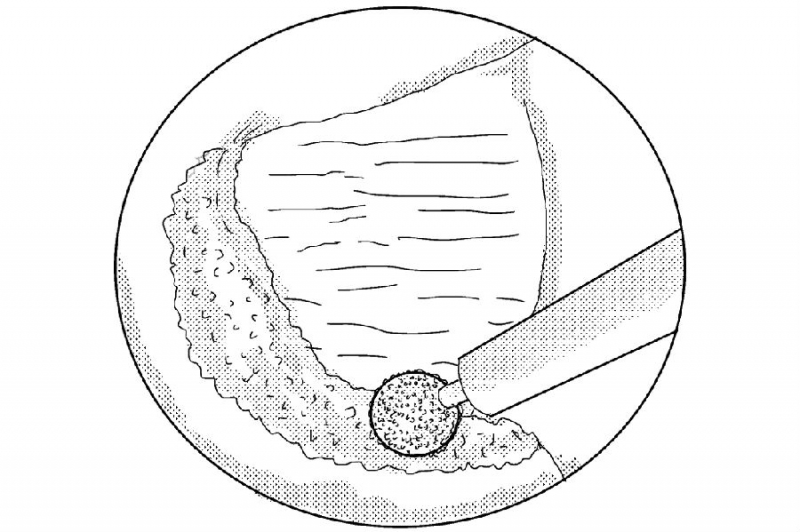

6. 使用骨凿将磨薄的下关节内缘凿除显露Corner和上关节突内缘;

7. 使用反向的椎板咬骨钳减压同侧Corner部位;

8. 减压的外界参考椎弓根内壁;